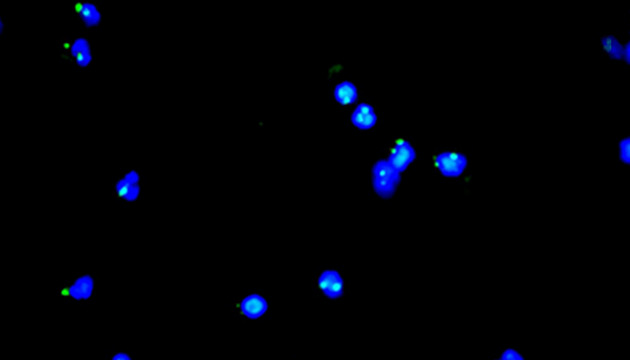

CTC检测用于上皮肿瘤,如胃肠癌、皮肤癌等。检测分四步:富集、CD45染白细胞、CK染CTC、DAPI染核。有DAPI、CK荧光且无CD45荧光,大核细胞为CTC;有DAPI、CD45荧光为白细胞。

CTC检测面临仪器通用性差、多色荧光阅片繁琐及高灵敏度成像难三大难点。新技术如微流控芯片有望取代专用仪器,提升富集效率。使用电动荧光显微镜搭配微流控,可更高效率进行CTC成像和阅片。另外为满足高灵敏度成像需求,建议配置优质LED光源、高效滤光片、半复消色差或以上物镜及高灵敏度相机。